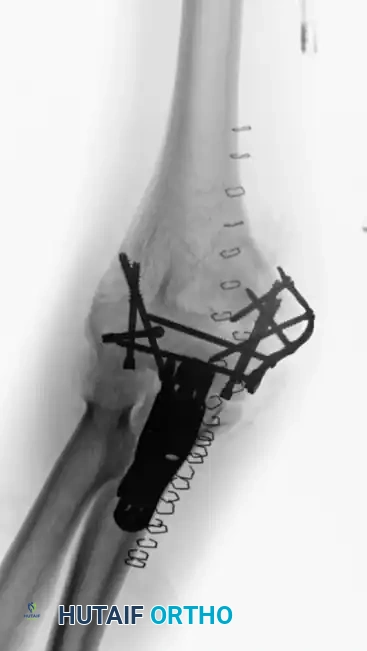

Plate fixation

Intraoperative view of definitive bicolumnar plate fixation. Notice the meticulous preservation of the soft tissue envelope.

Repair olecranon osteotomy

Repair of the olecranon osteotomy. Anatomic reduction of the chevron cut is critical to restore the articular congruity of the greater sigmoid notch.

Alternative view of repair

Final intraoperative view of the repaired olecranon osteotomy prior to layered closure.